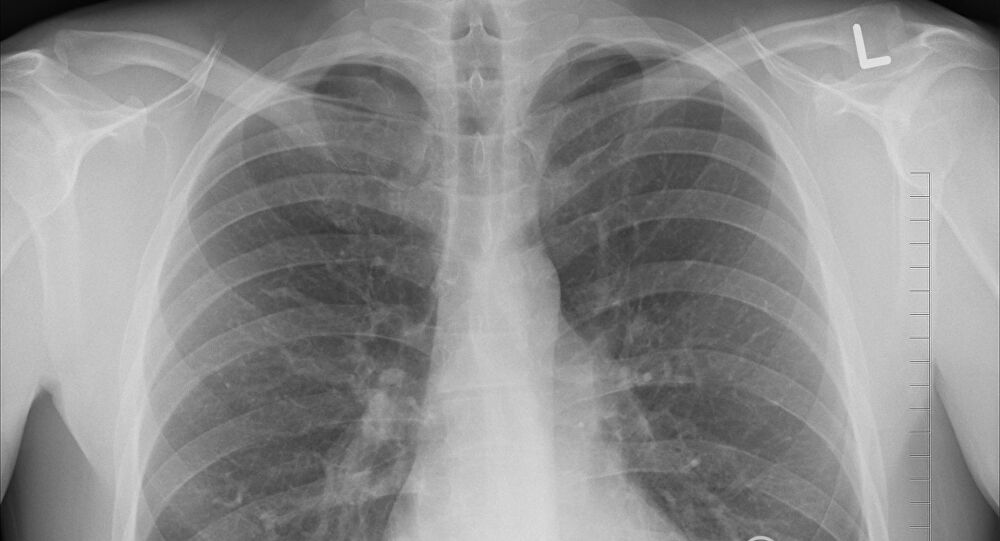

Овошјето и зеленчукот, како што е веќе добро познато, се многу здрави и го штитат организмот од многу болести. Но, јаболката и крушата имаат предност и кај хроничните белодробни заболувања кога ќе се споредат со другите видови овошје, заклучија истражувачи од Националниот институт за здравство во Билтовен во Холандија (National Institute of Health in Bilthoven, the Netherlands.).

Тие претпоставуваат дека секундарните растителни супстанции содржани во овие плодови – катехини (catechins), може да бидат одговорни за тоа. Точно 14.000 луѓе кои биле набудувани од тимот експерти и кои јаделе јаболка, страдале помалку од голема кашлица и оштетување на органите за дишење отколку другите, објави Б92.

Самите катехини (catechins), кои, на пример, се наоѓаат и во чајот и ги штитат срцето и крвните садови од болести, го немаат тој позитивен ефект кај белодробните заболувања.